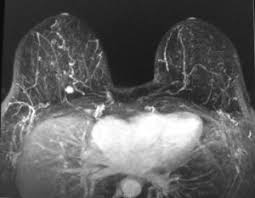

If these tests don't answer the quest. But not every woman who has been diagnosed with breast cancer needs a breast mri. Determining the extent of cancer after a new breast cancer diagnosis. It can also help detect breast cancer in women with breast implants and in younger women who tend to have dense breast tissue. An mri can be used to look for a disease, such as breast cancer. But there are also other reasons to have a breast mri. Inflammatory breast cancer affects breast tissue and can appear unusually dimpled or thick. Breast mri images are combined, using a computer, to create detailed pictures. A waiver of informed consent Mri scan is also used in breast screening for young women who are at higher risk of developing cancer. Dcis on mri may create an area of irregular enhancement of the mri dye into the breast. They're often easy to move around (mobile) and may be tender. A breast mri is a highly effective test.

Lobular breast cancer can be more difficult to see on imaging and scans. Recent research has found that mri can locate some small breast lesions sometimes missed by mammography. Your doctor may recommend a breast mri for the following: The dye collection in the breast can also look clumpy or appear in a section of the breast, depending on the involvement of dcis. Some benign conditions such as fibrocystic disease can look like cancer.

The Radiology Assistant Mri Of The Breast from radiologyassistant.nl Your doctor may recommend a breast mri for the following: A breast mri captures multiple images of your breast. This is why we ask questions about menstrual cycle and hormone therapies prior to your study. What does breast cancer look like on a mammogram? Dcis on mri may create an area of irregular enhancement of the mri dye into the breast. The features of a malignant breast condition on mri scan are often to do with the outer irregular borders of a lesion. An mri can be used to look for a disease, such as breast cancer. If you are at risk of getting a certain disease, your caregiver may want to do an mri to look for signs of the disease.

An mri can help find a disease of the lungs or show tumors (growths) in the chest. But not every woman who has been diagnosed with breast cancer needs a breast mri. The features of a malignant breast condition on mri scan are often to do with the outer irregular borders of a lesion. A rash isn't the only visual symptom of inflammatory breast cancer. Any area that does not look like normal tissue is a possible cause for concern. A breast mri scan might also be used to assess the size of the cancer to check which kind of surgery is possible. They work to destroy the tumor or slow down the growth of cancer cells. This appears most commonly as streaking, known as linear enhancement. On the flip side, there are benign (not cancerous) breast changes which can mimic breast cancer as well. This means that the test finds a mass or other change that seems to show cancer but it is not cancer. Breast mri images are combined, using a computer, to create detailed pictures. What does breast cancer look like on a mammogram? The dye collection in the breast can also look clumpy or appear in a section of the breast, depending on the involvement of dcis.